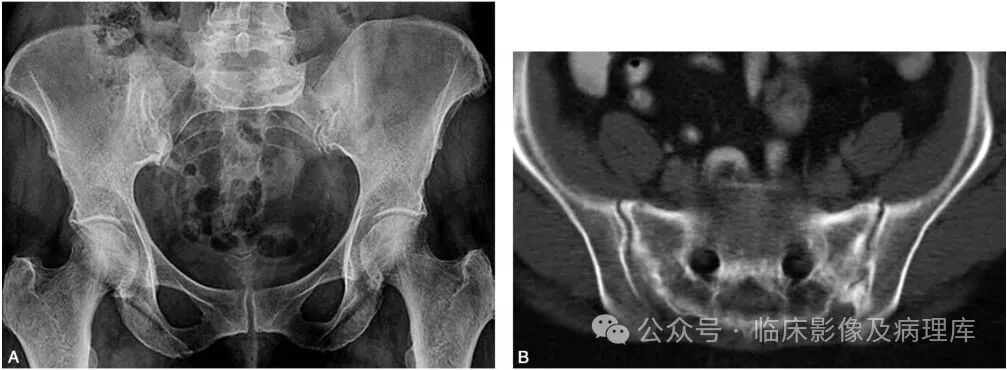

女性,65岁,宫颈癌放疗后。A.骨盆正位片:骨盆诸骨示弥漫性骨质疏松改变,右侧骶骨耳部骨密度减低明显;B.骶骨CT平扫:骶骨弥漫性骨质疏松,双侧骶骨耳部隐见弯曲线样低密度影,周围示片状骨质硬化影。骶骨右前缘示局限性皮质中断;C、D.冠状位SE T1WI和脂肪抑制FSE T2WI示双侧骶骨耳部弯曲线样低信号影,周围见大片状长T1长T2水肿信号;E.核素扫描(后面观):双侧骶骨耳部核素浓聚,以右侧明显